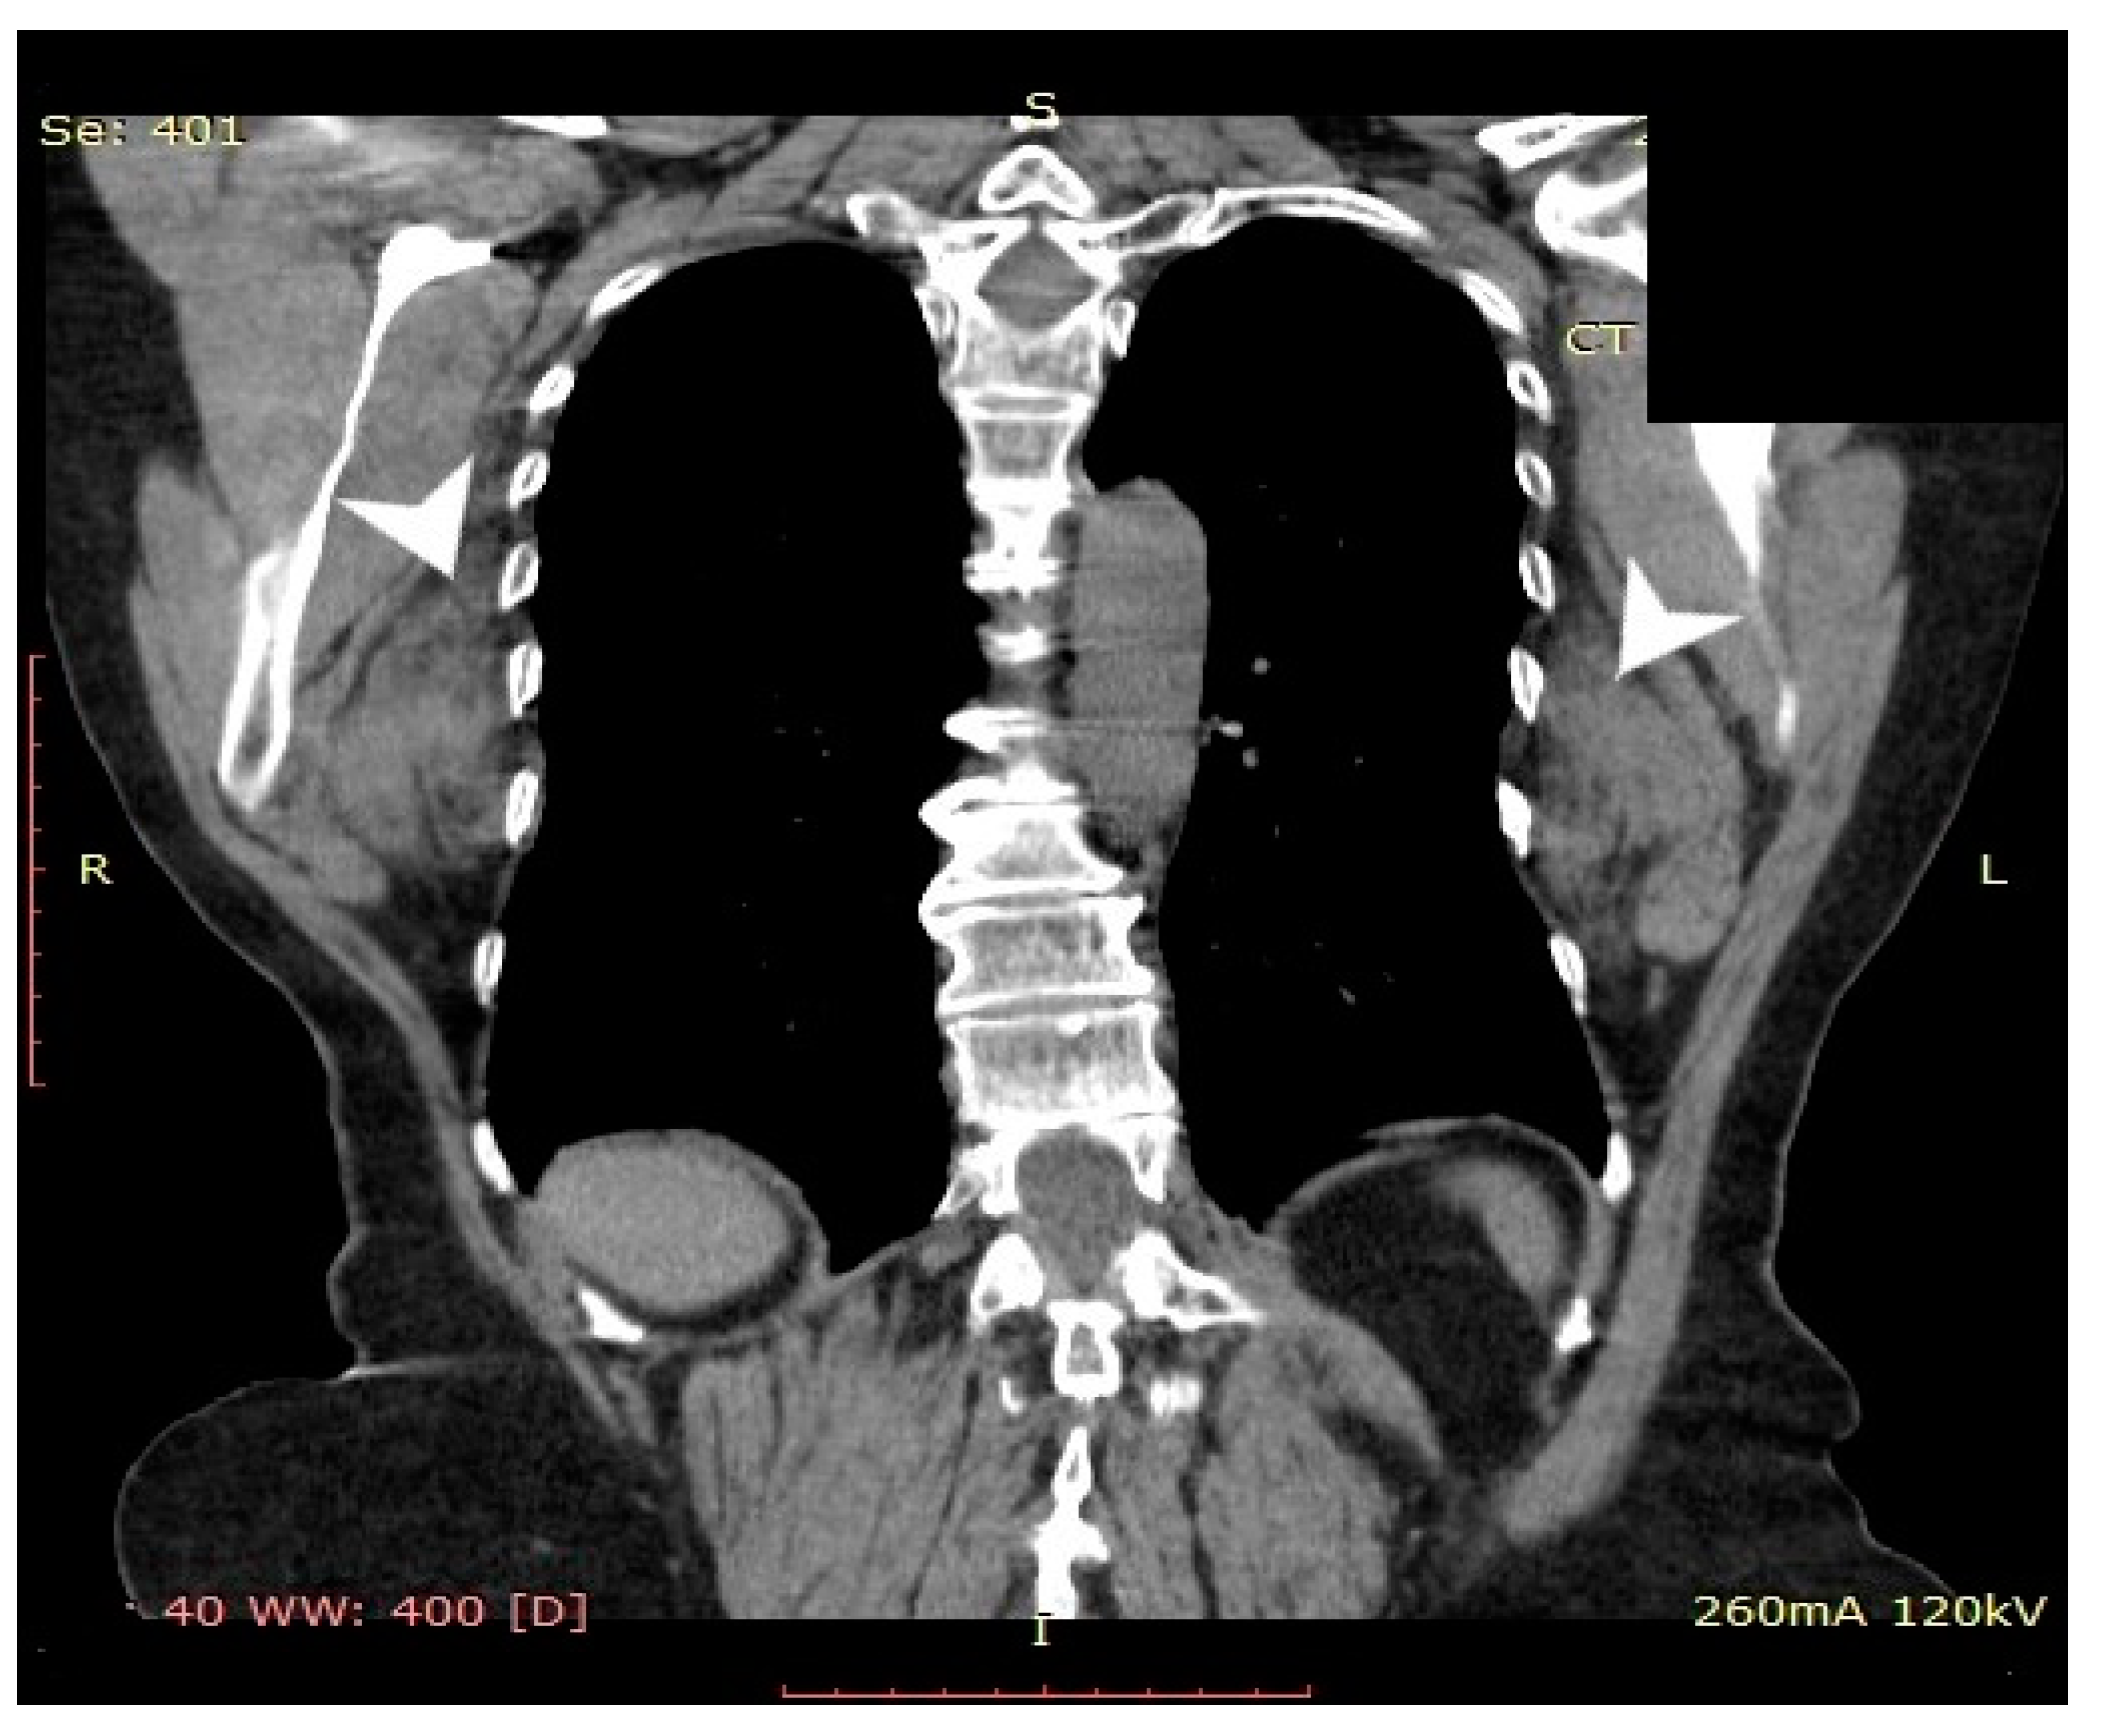

2. Case Presentation